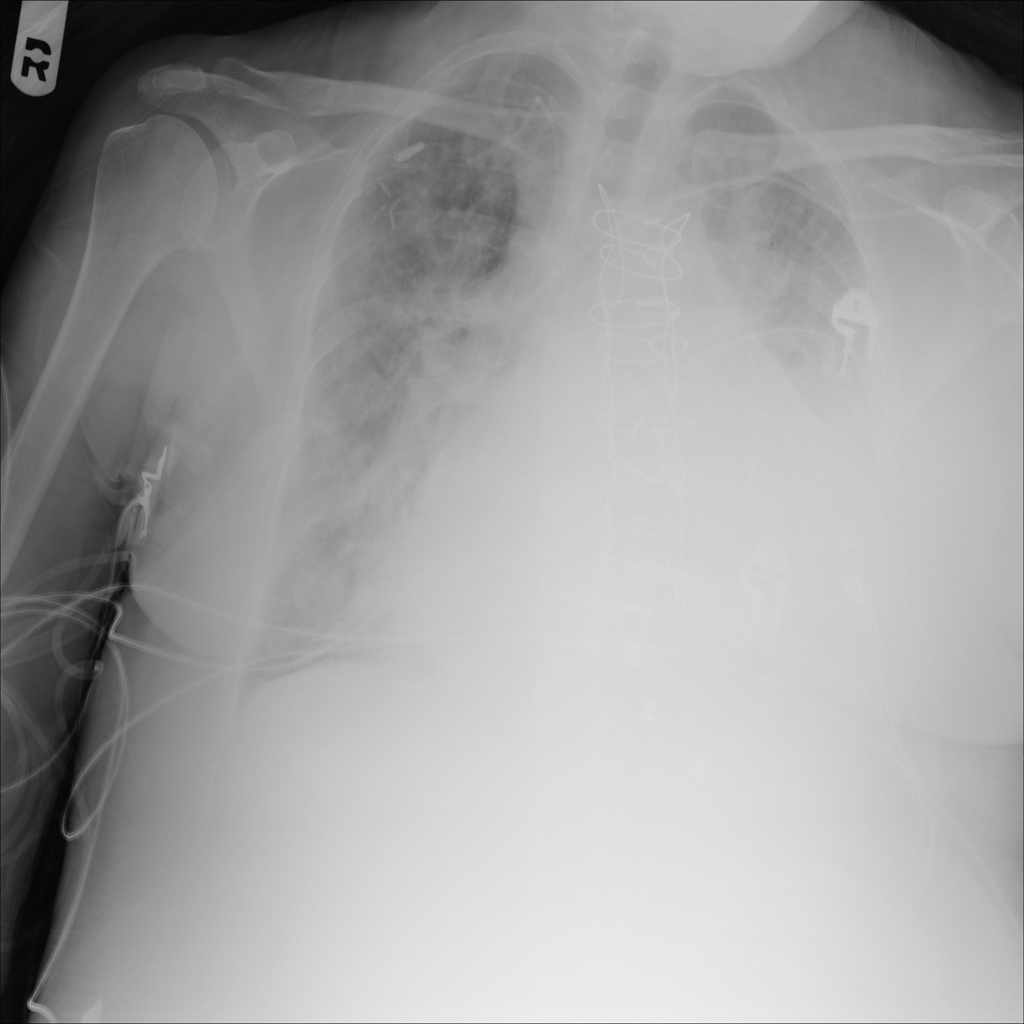

PAT-3384 · IMG-000Cardiomegaly

PAT-3384 · IMG-000

AP